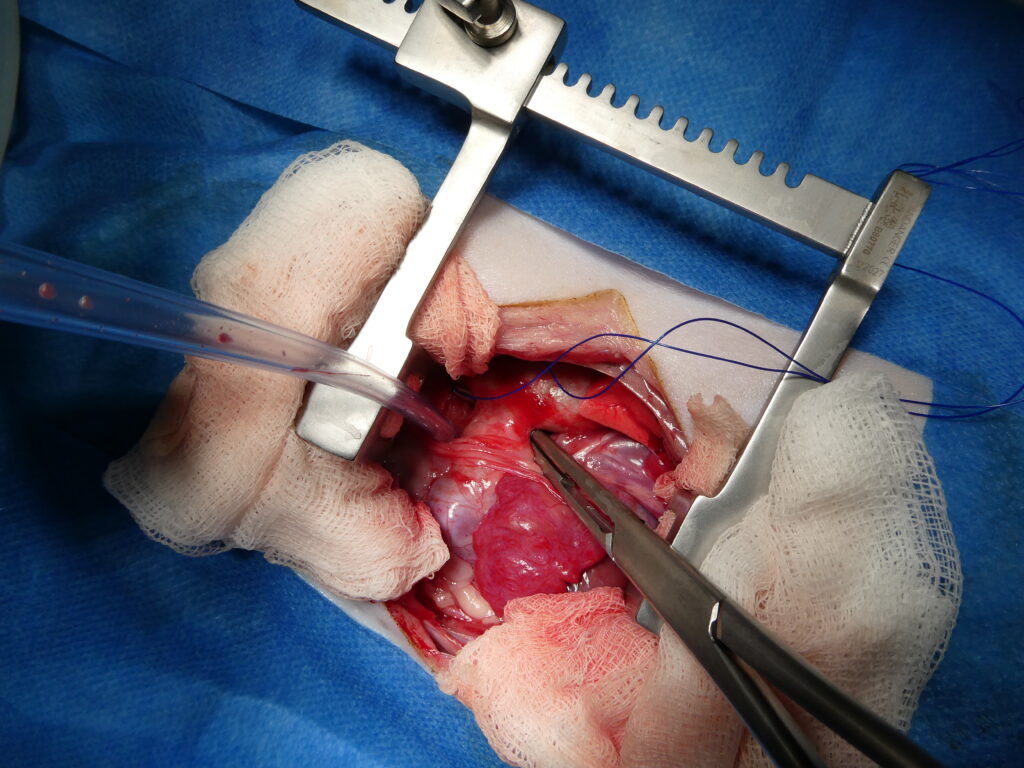

Chirurgie de persistance du canal artériel par ligature.

À gauche, ouverture du thorax par thoracotomie avec maintien de l’écartement costal à l’aide d’un écarteur de Finochietto, permettant un accès direct et sécurisé au médiastin.

Au centre, dissection minutieuse des structures vasculaires et passage d’un fil de suture à l’aide d’un clamp spécifique en arrière du canal artériel persistant, en vue de réaliser une double ligature.

À droite, canal artériel complètement ligaturé par deux nœuds successifs, interrompant la communication anormale entre l’aorte, située au-dessus de la ligature, et le tronc pulmonaire, situé en dessous, avec un résultat immédiat et durable lorsque la ligature est complète.